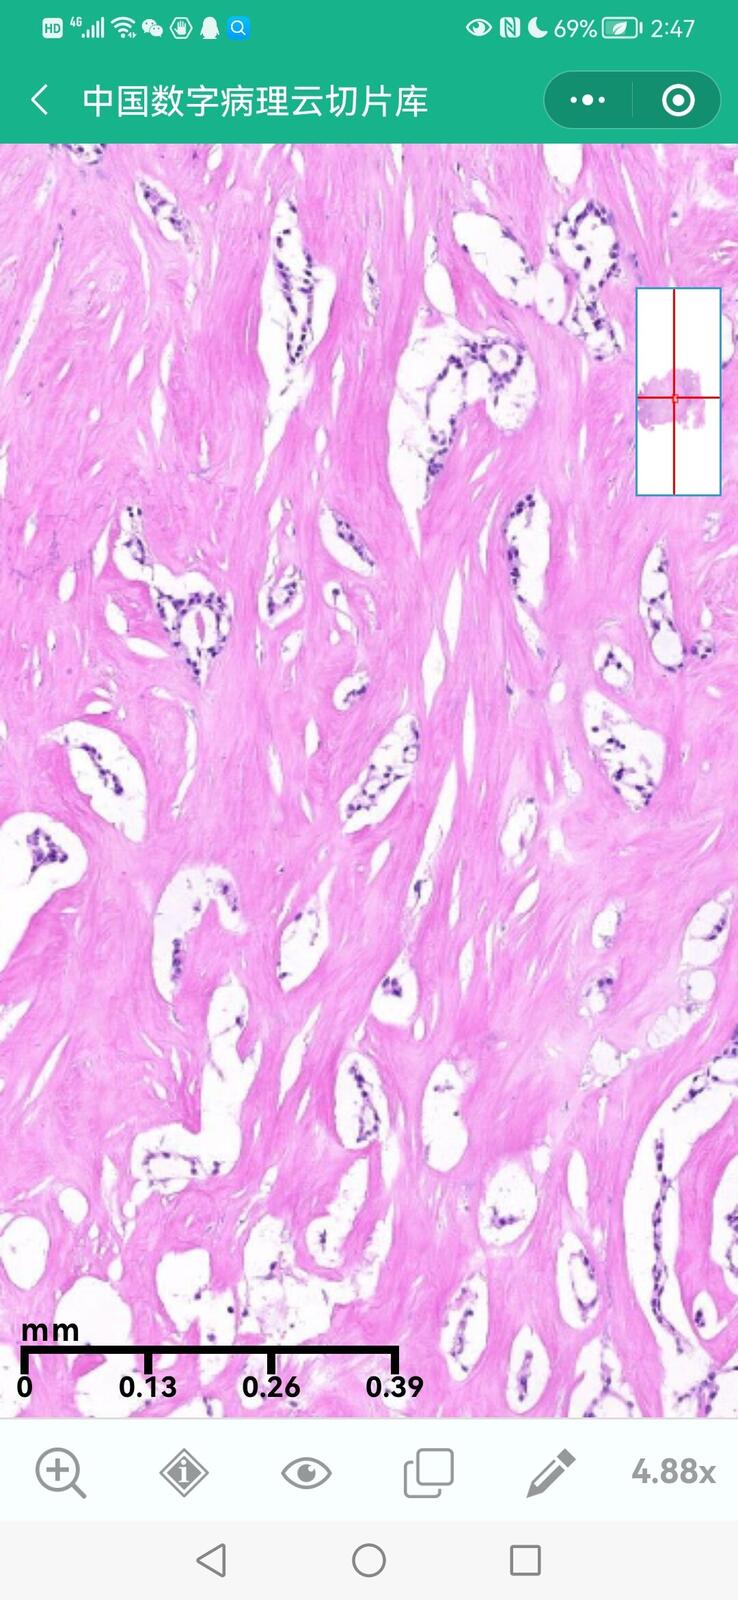

乳腺黏液性囊腺瘤伴导管内癌

乳腺多形性脂肪肉瘤

乳腺叶状囊肉瘤

乳腺分泌性癌(29岁)